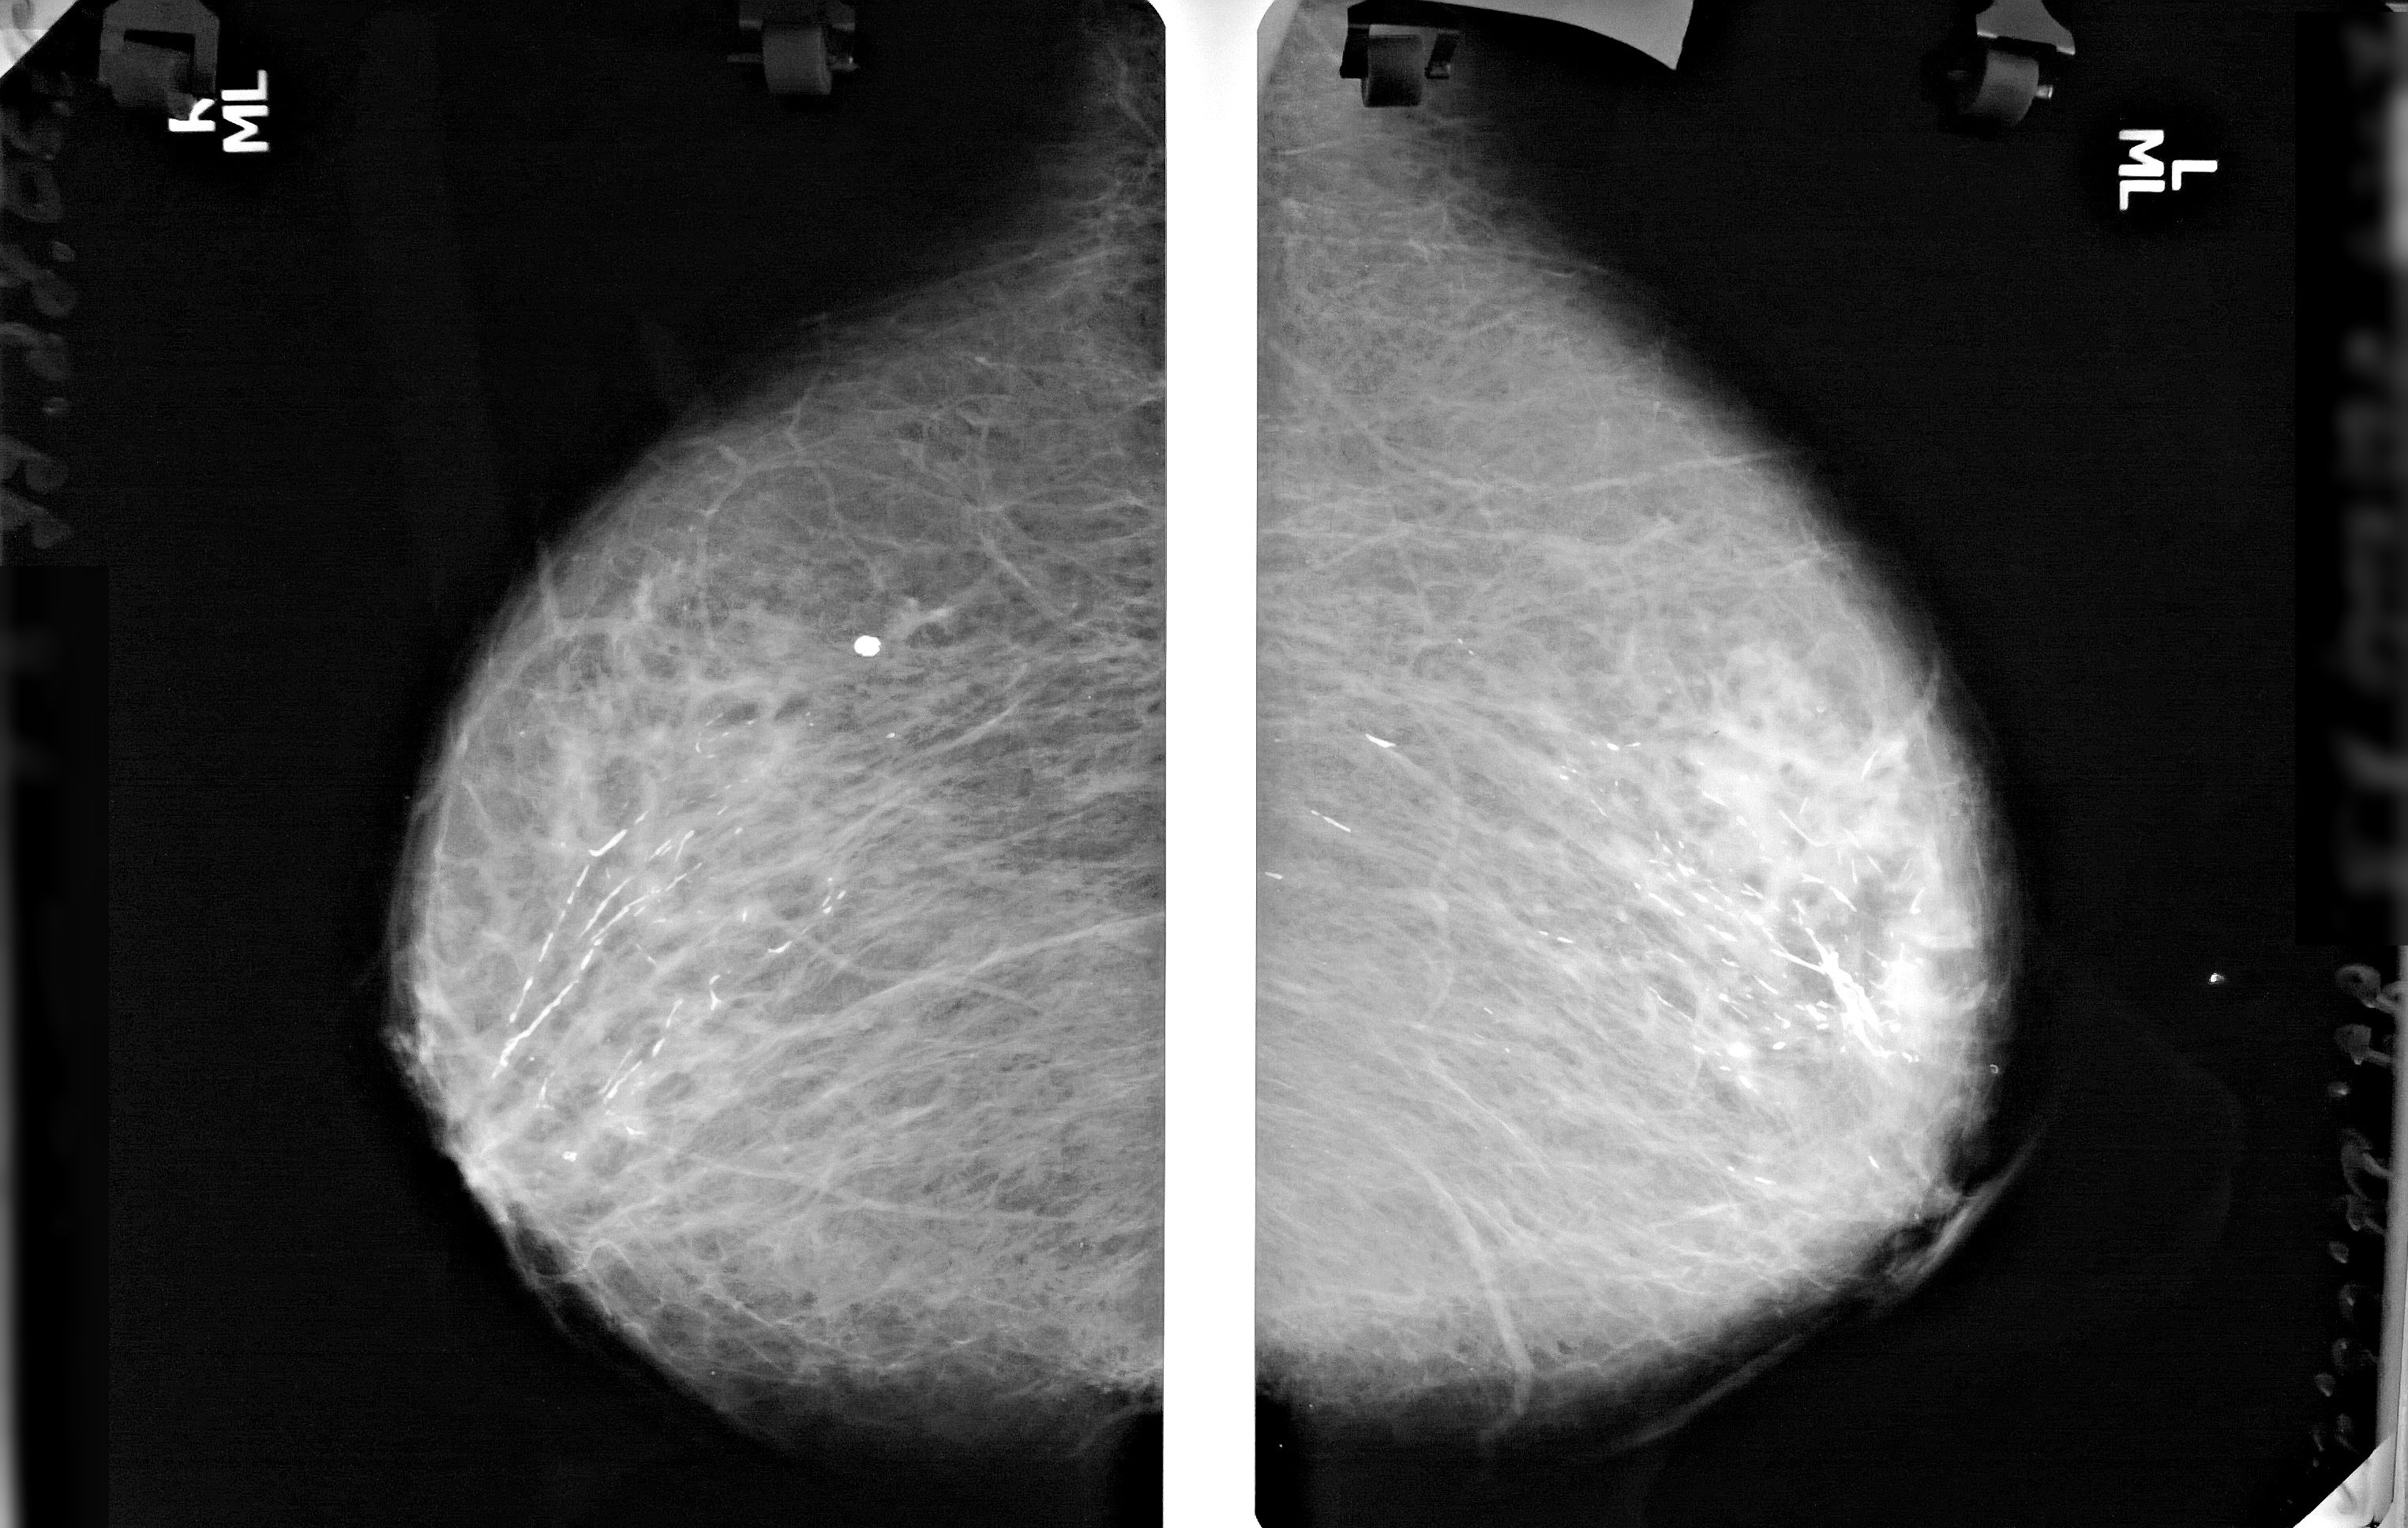

Что такое маммография: важность, процесс и результаты